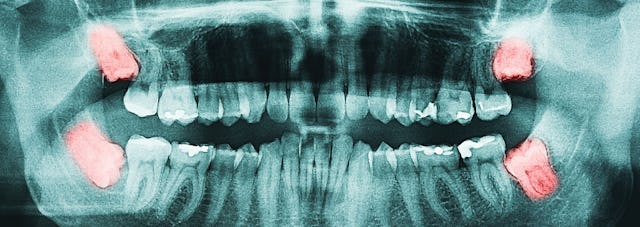

Die Weisheitszähne (im Bild rosa eingefärbt) sind die letzten Zähne im Mund und werden auch als Achter (8er) bezeichnet. 8er deshalb, weil sie an achter Position stehen, wenn man beim ersten Frontzahn anfängt zu zählen. Alle Weisheitszähne sind auf dem Bild im Durchbruch behindert. Der am meisten verlagerte Weisheitszahn auf dem Bild ist derjenige unten links, der sogenannte 48 (vier-acht). 48 deshalb weil sich dieser Achter im vierten Quadranten befindet (die Quadranten werden von oben links nach unten rechts im Uhrzeigersinn beziffert). Der 48 ist unten rechts und nicht unten links wie man meinen könnte, weil die Röntgenbilder gemäss internationaler Gepflogenheit so dargestellt werden wie der Zahnarzt den Patienten sieht und sind somit spiegelverkehrt.

Das aufgeführte Panorama-Bild (ganz oben) verdeutlicht die Position der Weisheitszähne und zeigt auch, wieso es zu einer geschwollenen Backe kommen oder beim oberen Weisheitszahn zur Schwellung bis unter das Auge kommen kann. Im Unterkiefer kann die Entzündung entsprechend in den Mundboden eindringen. Am Häufigsten ist allerdings eine Vorwölbung an der Wange, welche als geschwollene Backe wahrgenommen wird.